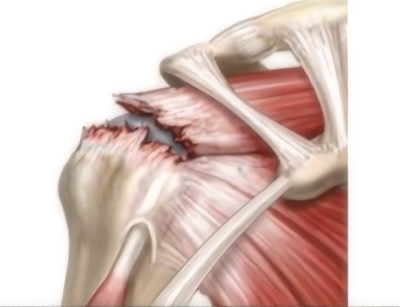

肩袖撕裂示意图

李良军主任解释,肩关节是人体活动度最大的关节,肩袖是人体肩部运动中非常重要的结构,由冈上肌、冈下肌、小圆肌和肩胛下肌这四块肌肉的肌腱共同组成。它像袖子一样包裹着肩部,帮助我们的肩膀完成抬举、旋转等动作。肩袖损伤主要表现为患肢抬举无力,主动活动受限,洗脸、梳头、穿衣等日常生活受影响;反复发作或持续的肩关节疼痛,夜间尤为明显,疼痛还可能放射至上肢。